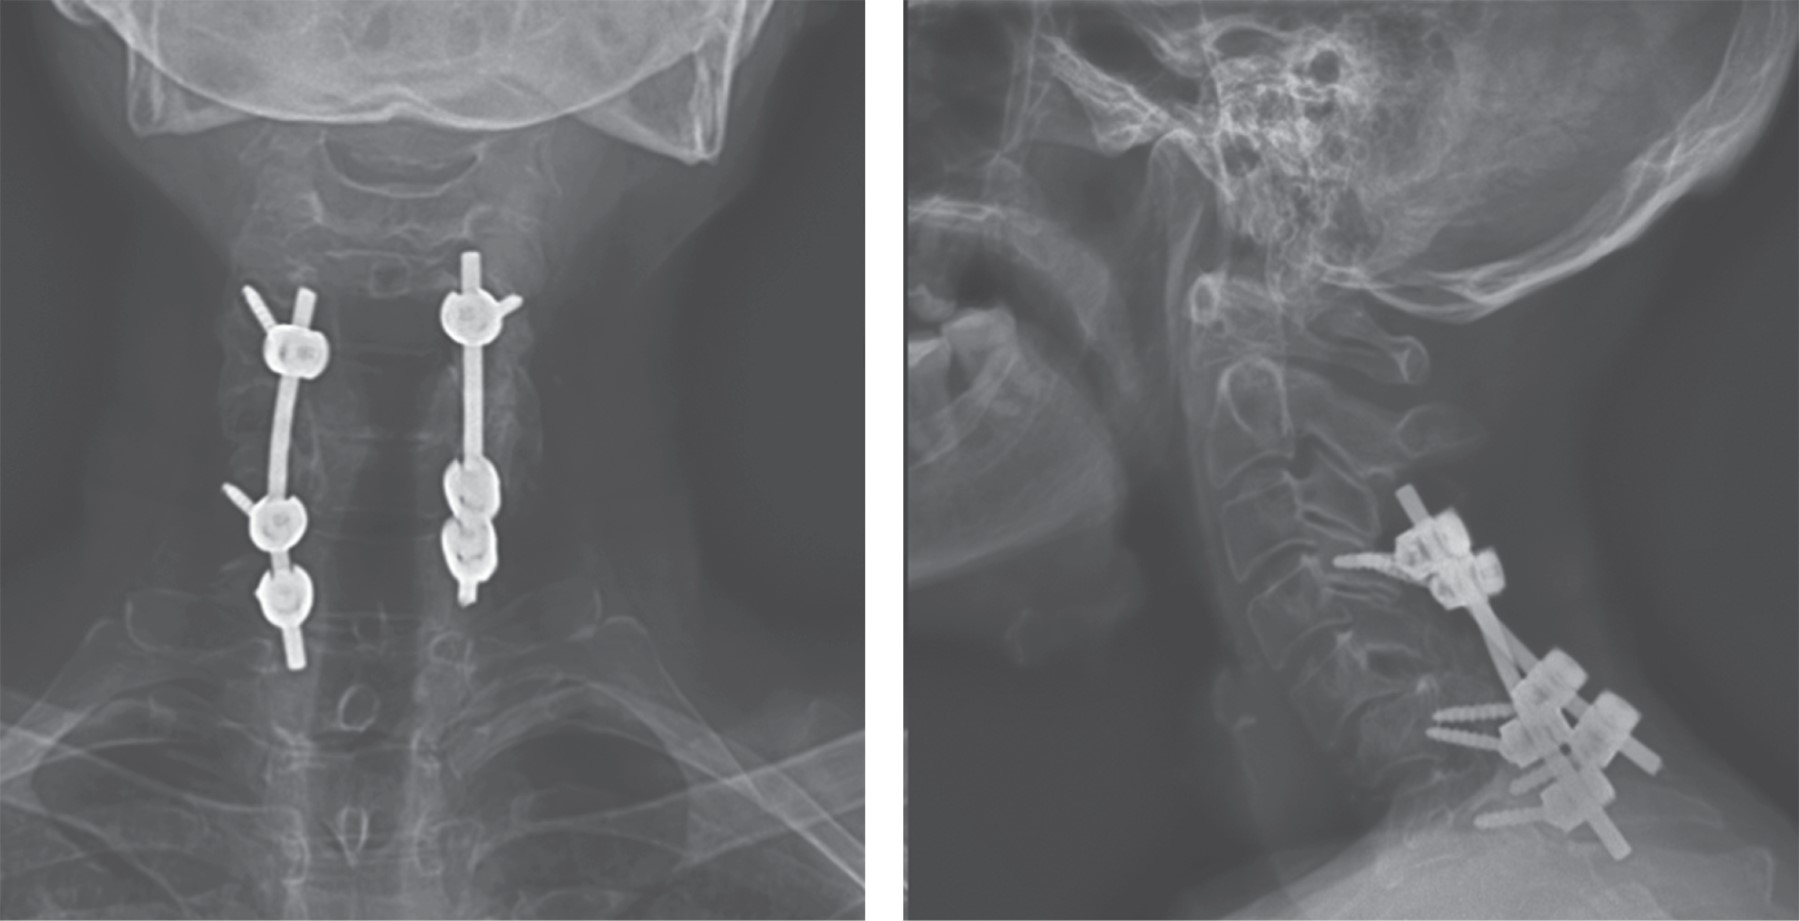

Subaxial cervical spine luxation is a frequent entity in polytraumatized patients, regularly accompanied by neurological injuries such as paraplegia or quadriplegia, requiring urgent surgical treatment in order to stabilize, align and decompress the nerve structures, sometimes it is not possible to perform this type of procedure early due to the general conditions of the patient or the conditions of the hospital units, leading to a late treatment, however, undiagnosed luxation occur, or in the worst case scenario, an inadequately treated injury with poor results that lead to an unsatisfactory evolution of the patient, with chronic pain and neurological deficit. We analyze the case of a patient with subaxial cervical spine luxation, with torpid evolution, requiring a new intervention two years after her injury, performed in three specific sequential times, achieving the patient's recovery and motor functionality.REFERENCES